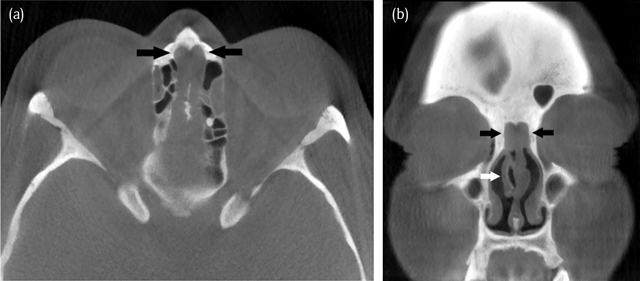

Figure 1

Axial (a) and coronal (b) CT images in bone window settings demonstrate the typical imaging findings. Bilateral opacification of the olfactory cleft leading to a total width of 1 cm (distance between the black arrows). The sharply delineated soft-tissue mass (black arrows) originate anteriorly and superiorly from the middle concha (white arrow). There is bone remodelling but no bone erosion.